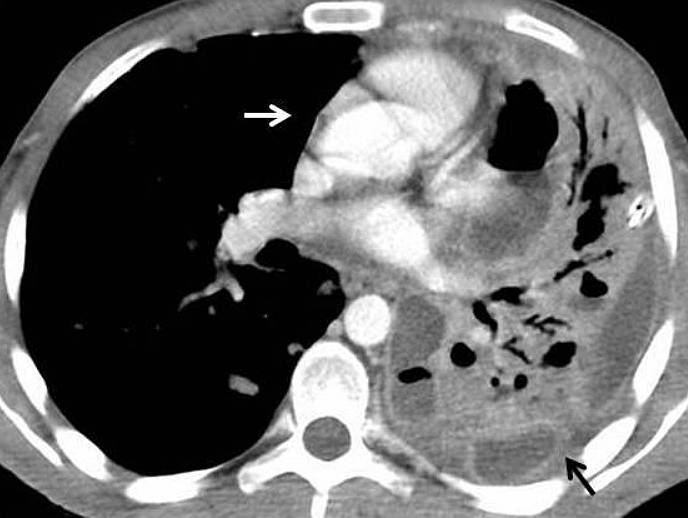

Also, CT revealed a loculated left pleural effusion with thickened and enhanced visceral and parietal pleura (the split pleura sign), suggestive of empyema (Fig. 3). There was no lymphadenopathy.